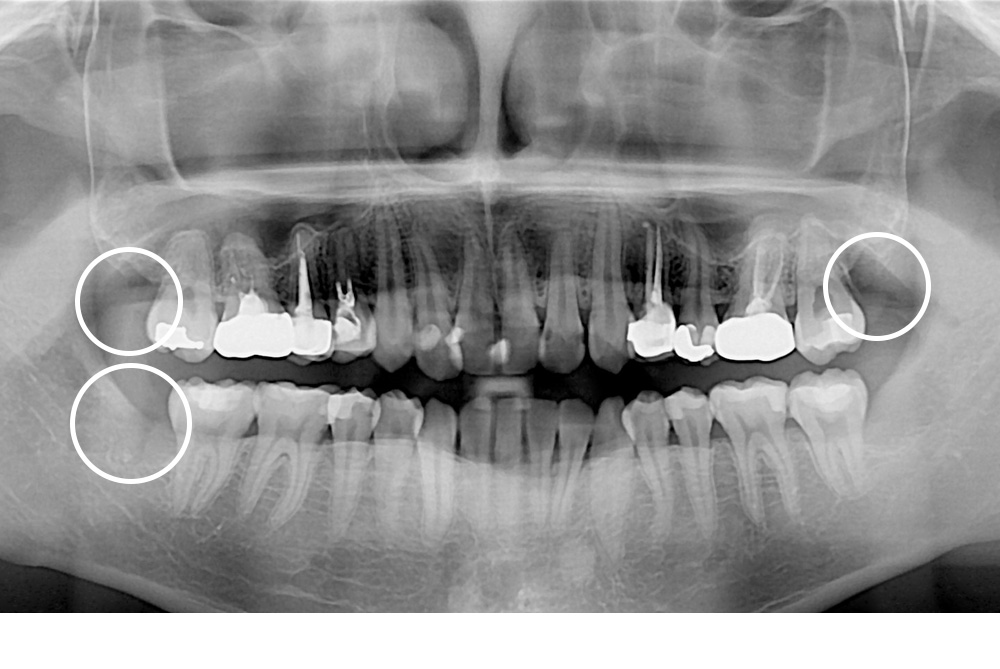

[사랑니] 매복 사랑니 발치

치료후 : 2020-06-26

세종치과는 구강악안면외과학 박사이신 원장님이 발치하는 치과입니다.